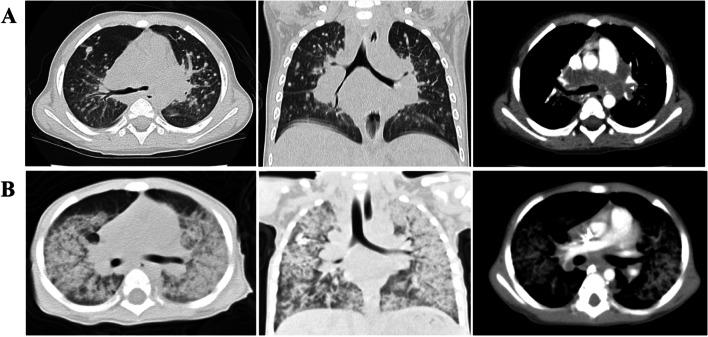

There were seven boys with age ranging from 4-20 months (median age, 13 months). Four of the seven respiratory infections were caused by Talaromyces marneffei(T. marneffei). Two patients had viral infections caused by cytomegalovirus (CMV) and human adenovirus respectively. One patient had a mixed infection caused by Pneumocystis carinii and CMV. Except for one child who died of respiratory failure, one patient received hematopoietic stem cell transplantation (HSCT) and recovered well, the other five patients survived with regular infusions of intravenous immunoglobulin (IVIg) during the follow-up period. Six patients had reduced antibody levels, especially IgG, IgA, and IgE levels. Increased serum IgM levels were detected in four cases, and three cases presented normal IgM levels at onset. All children were diagnosed with XHIGM with CD40LG variation. Three novel mutations were identified in the present study.

有 7 名男孩,年龄 4-20 个月(中位数年龄 13 个月)。7 次呼吸道感染中有 4 次由 Talaromyces marneffei(T. marneffei)引起。2 例患者分别由巨细胞病毒(CMV)和人腺病毒引起的病毒感染。1 例患者发生卡氏肺孢子虫和 CMV 混合感染。除 1 例因呼吸衰竭死亡的患儿外,1 例接受造血干细胞移植(HSCT)后恢复良好,其余 5 例患儿在随访期间定期输注静脉注射免疫球蛋白(IVIg)存活。6 例患儿抗体水平降低,尤其是 IgG、IgA 和 IgE 水平。4 例患儿血清 IgM 水平升高,3 例患儿起病时 IgM 水平正常。所有患儿均被诊断为 XHIGM,CD40LG 变异。本研究共发现 3 种新突变。